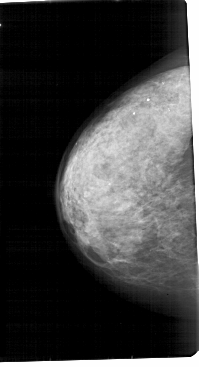

A_1810_1.LEFT_MLO

LEFT_MLO LINES 5491 PIXELS_PER_LINE 3256 BITS_PER_PIXEL 12 RESOLUTION 43.5 NON_OVERLAY